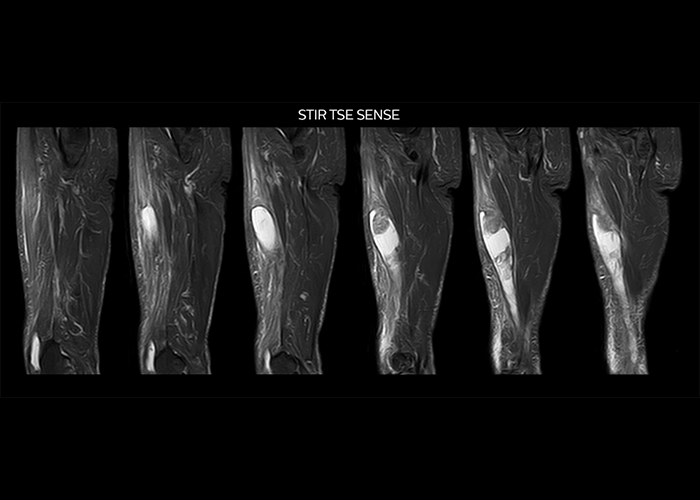

“To avoid coil changes we plan examinations of similar anatomies back to back, such as head and spine. Multiva helps us here a lot because coils don’t need to be changed frequently. Moreover, thanks to parallel imaging technology and 16-channel HeadSpineTorso and 8-channel MSK coils we are able to achieve excellent image quality. In this way Multiva helped us to increase both image quality and productivity.”

“Neurological cases, such as brain and spine imaging, represent the largest share in our MR scanning, followed by musculoskeletal cases. In general, we use simple and basic imaging protocols. But occasionally, we use advanced techniques for problematic cases if necessary.